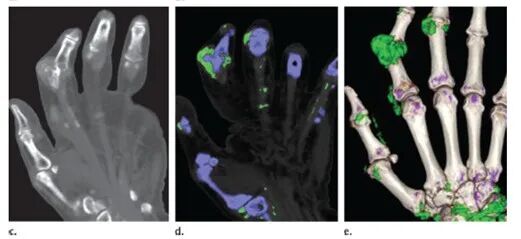

目前,惠州三院可以檢測(cè)別嘌醇過(guò)敏基因,還有專(zhuān)門(mén)為痛風(fēng)病人而設(shè)的關(guān)節(jié)彩超,以及全惠州唯一一部能探測(cè)出尿酸結(jié)晶的雙能CT,能更好地為痛風(fēng)患者的健康保駕護(hù)航!

痛風(fēng)彩超圖像

痛風(fēng)CT影像